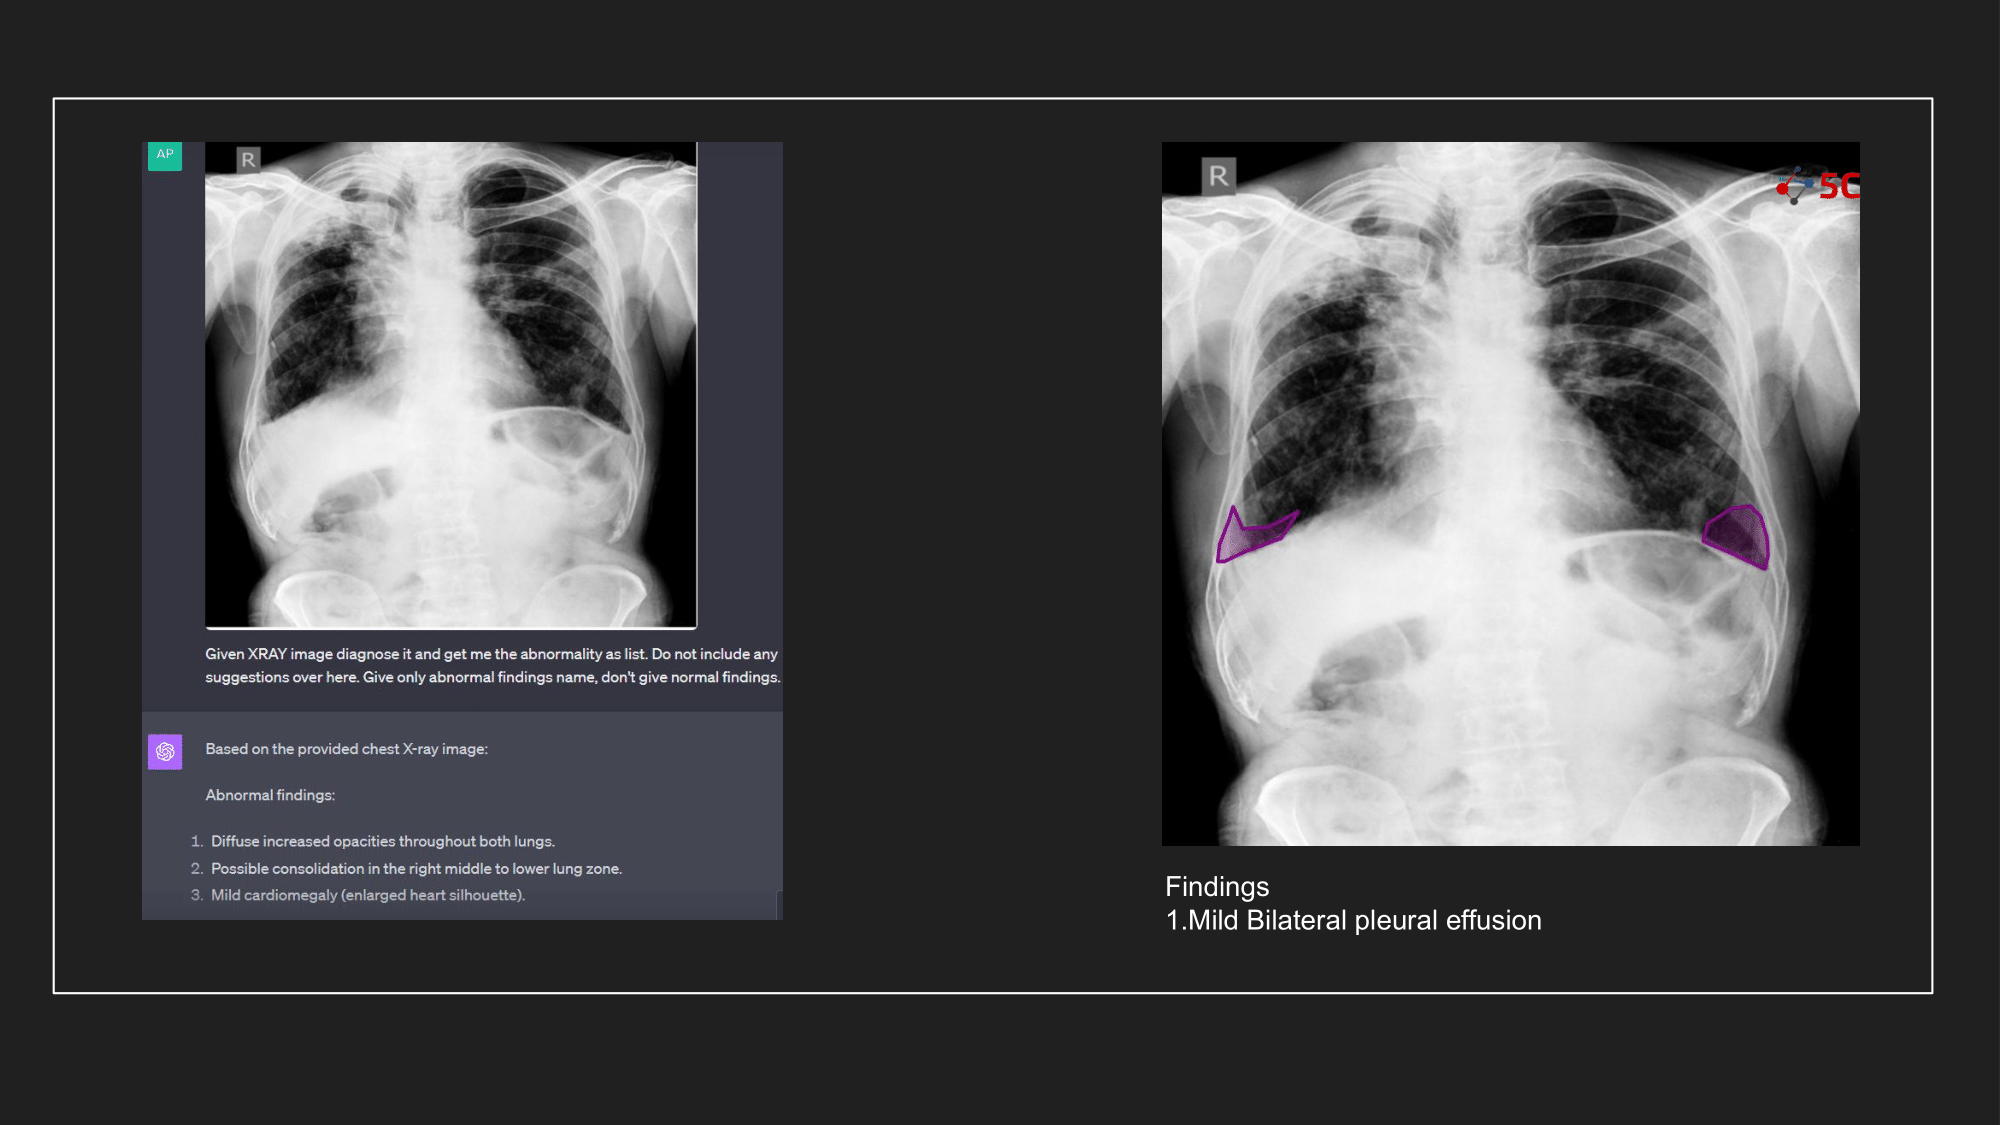

To gauge GPT-4V's prowess in detecting pleural effusion, an experiment was conducted with 10 random chest X-rays known to have pleural effusion. The XRays were sent to GPT-4V, Radiologists as well as to 5C's AI.

Presented below are the results from the experiment.

The output from GPT-4V and from 5C's AI model for the Chest XRays are provided at the end of the post.